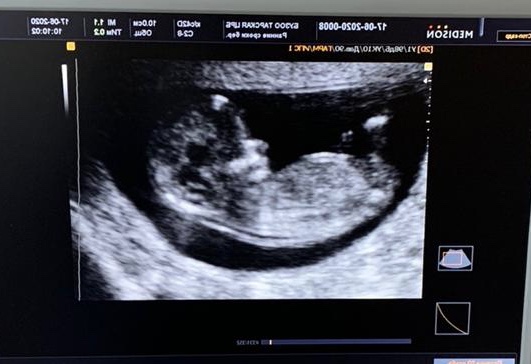

Видно видно и очень отчётливо)

Ну да, вверх торчит бугорок)))

Думаю мальчик)) Нам тоже в 13 недель, предположили мальчика) видно что мальчик?)

То, что мальчик нам подтвердили уже💙 Я по фото не разбираюсь вообще😂 Вы уже ходили смотреть или ждёте скрининга?

Именно в том месте, которое должно указывать кто там, мальчик или девочка, очень мутное качество 😁✊🏼